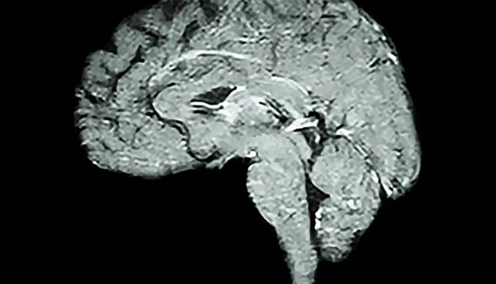

Cerebral ischemia is defined by iNADequate blood supply to neural tissue leading to an oxygen shortage. A person will lose consciousness after 10 seconds of interrupted blood flow to the brain, and other symptoms of cerebral ischemia include impairments in vision, body movement, and speaking abilities. Previous research has indicated treating mice with a molecule called Nicotinamide Mononucleotide (NMN) protects against ischemic brain damage and promotes cellular health by reducing fragmentation of the cell’s powerhouse, the mitochondria. However, the molecular mechanism by which this occurs remains unclear.

Recently, a group of scientists from The University of Maryland and the Veterans Affairs Maryland Health Center published a study in Experimental Neurology where they demonstrated that supplementing NMN to mice with cerebral ischemia improved mitochondrial health by reducing molecular tags called “acetylation” on proteins in the mitochondria. The administration of this molecule also reduced mitochondrial fission, a molecular process whereby the mitochondria split apart so that they are smaller in size, and reduced the quantity of reactive oxygen species–chemically reactive and physiologically damaging molecules–in cells.